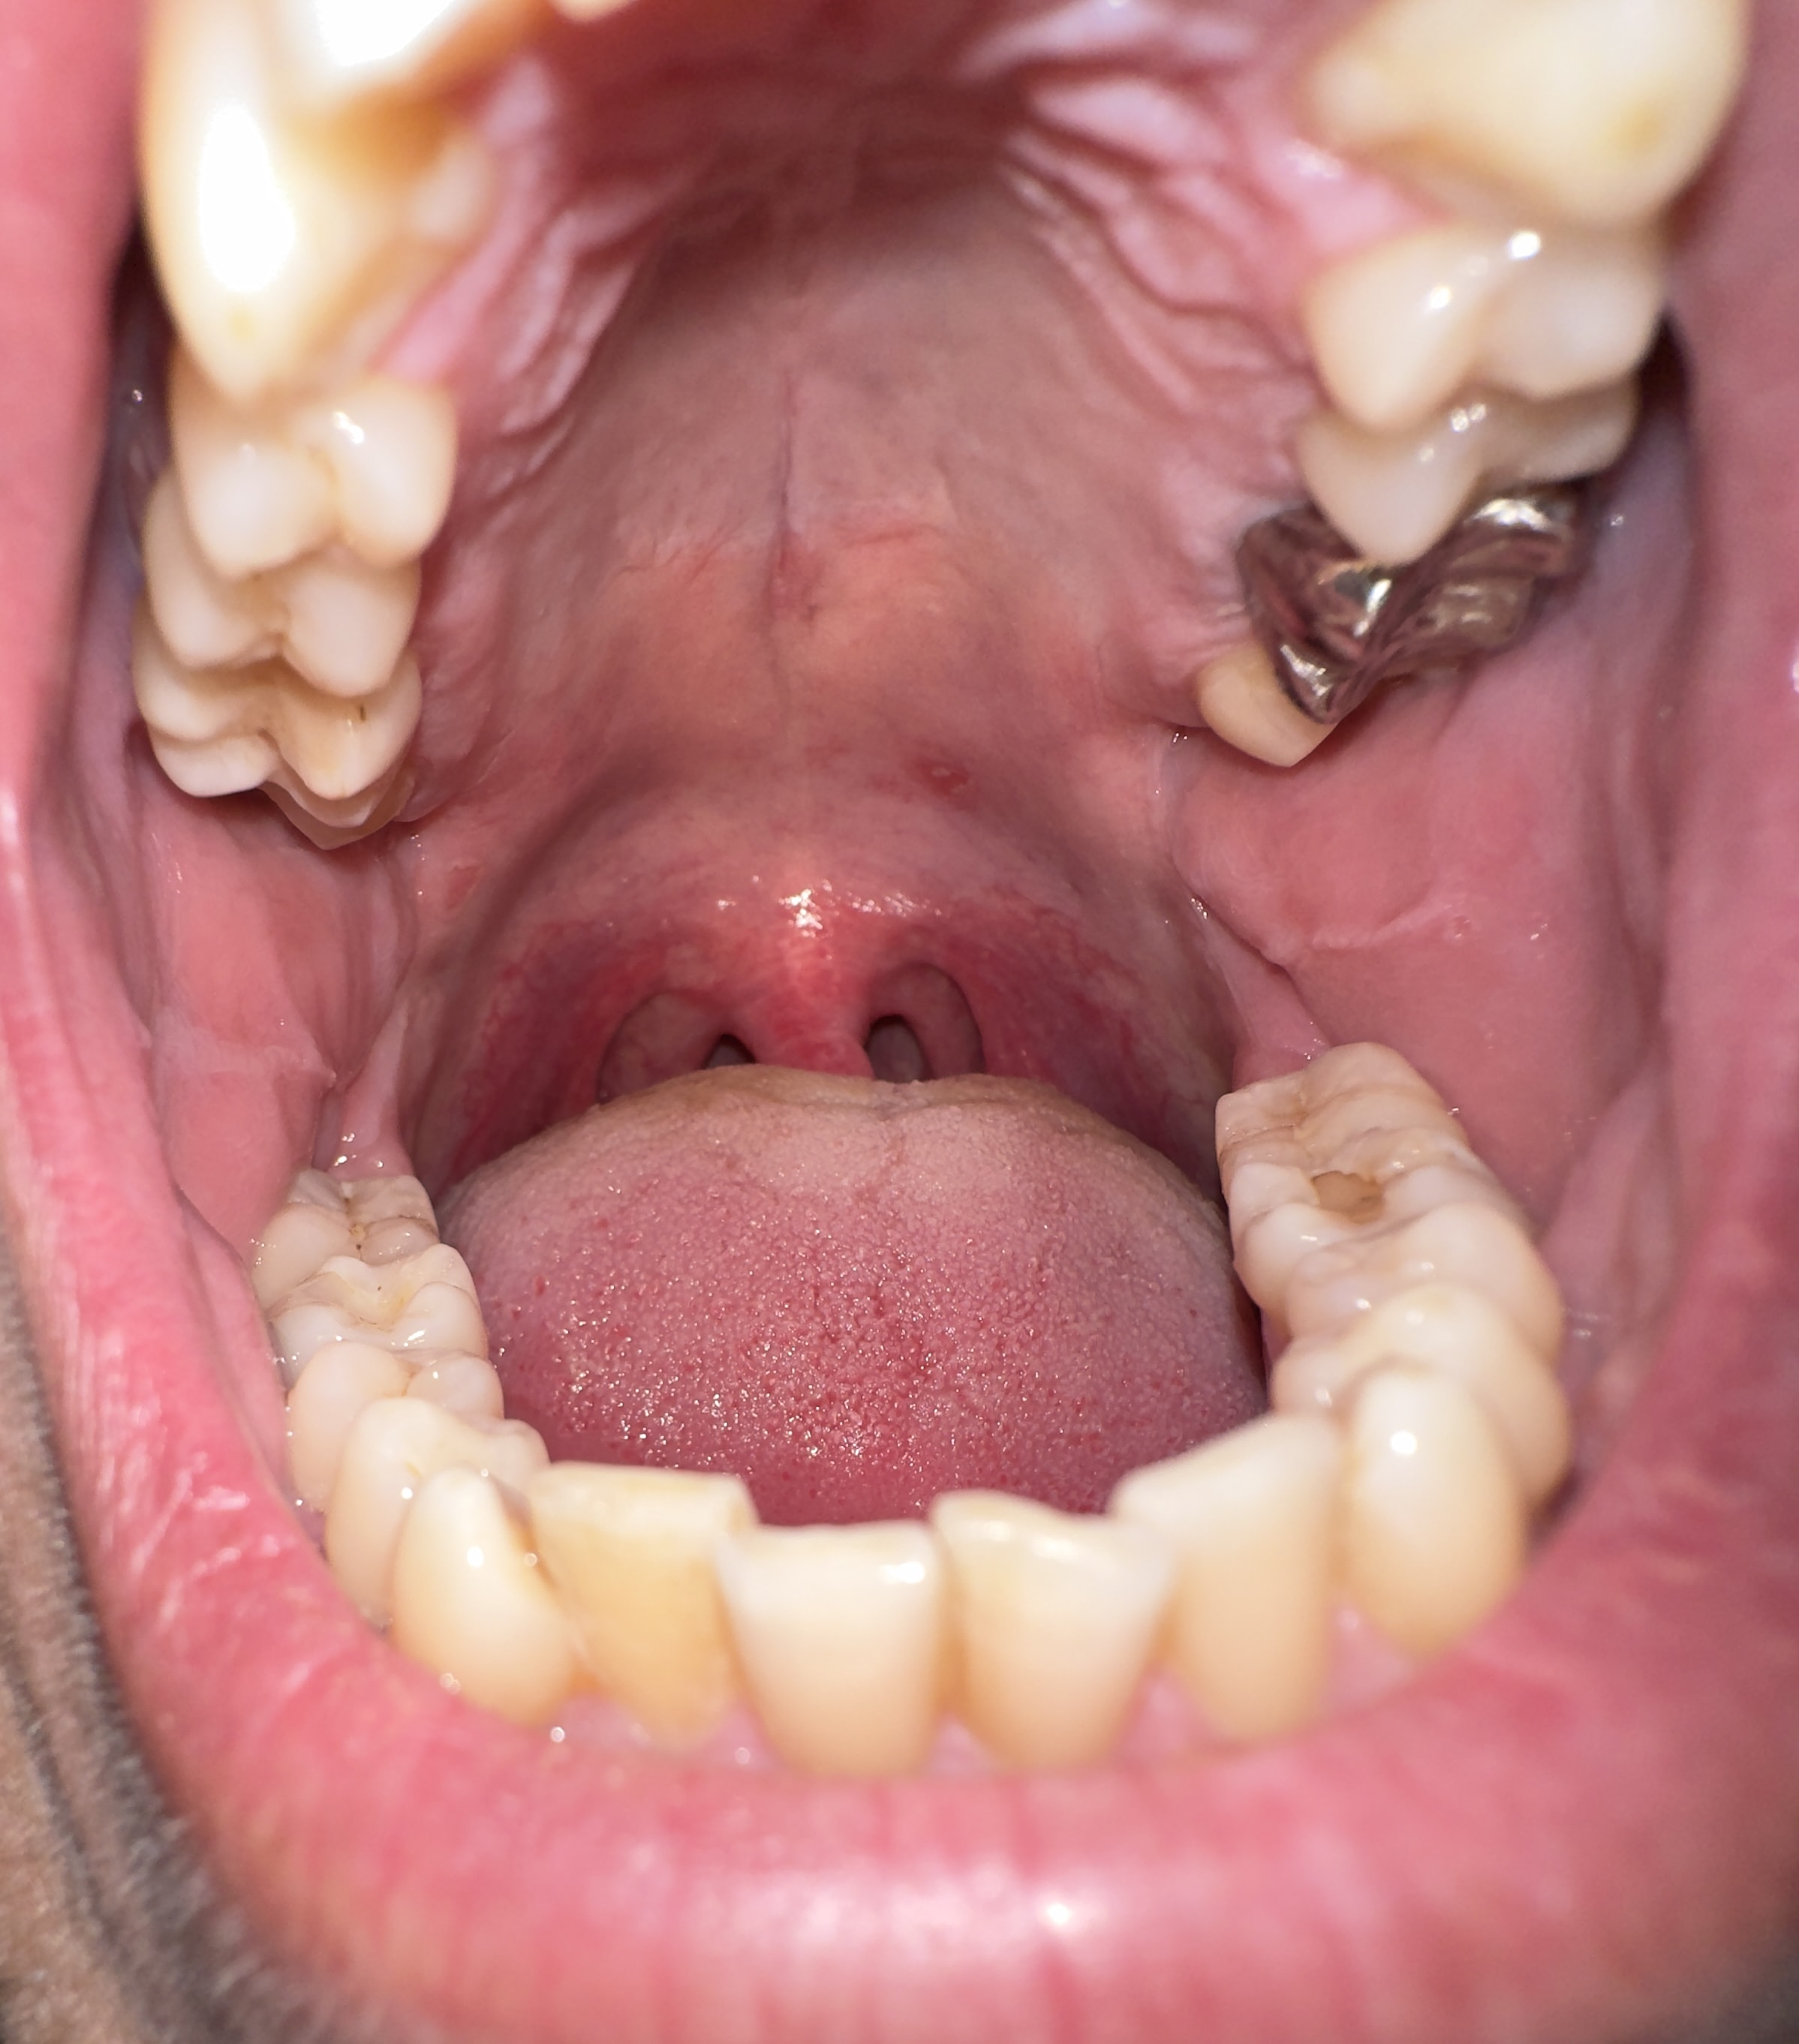

mein Mundschleimhaut ist immer gereizt. War schon beim Hausarzt und 2 verschiedene HNO Ärzte und meinten das es ein normale Mundschleimhaut ist. Das was ich markiert habe, kommt und geht. Nach Zähne putzen schön sauber aber nach dem Essen kommt es wieder ? Bin stark Raucher und 37 Jahre alt. 1x geimpft.

Danke für ihr Antwort aber mache mir Sorgen zwecks diese weiße Punkte/stellen. Ist meistens da wo meine Weisheitszähne waren. Schaut aus wie Pilz ?

ist kein pilz, nur fibrin von kleinen wunden und ev. infektionen durch deine finger im mund.